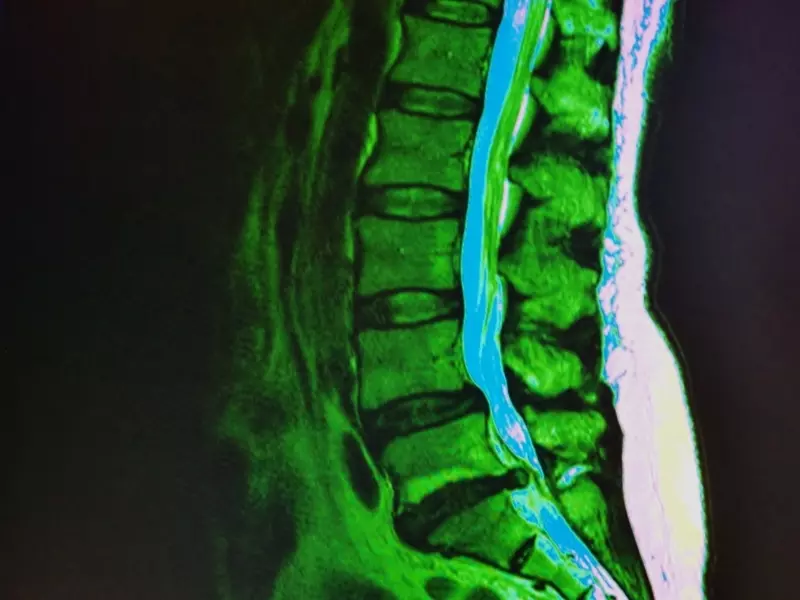

Choroba Mortona, neuralgia Mortona, zwana też potocznie nerwiakiem Mortona, to neuropatia uciskowa nerwów palców z towarzyszącym jej włóknieniem okołonerwowym. Nazwa „nerwiak” bywa dość myląca, ponieważ sugeruje niezłośliwy nowotwór nerwu obwodowego, a w przypadku choroby Mortona prawdziwy nerwiak występuje niezwykle rzadko. Najczęściej choroba spowodowana jest podrażnieniem nerwu i dotyczy prawie zawsze drugiego i trzeciego nerwu palcowego wspólnego [1, 3–5].

Neuralgia Mortona znacznie częściej występuje u kobiet, szczególnie po 50. roku życia, niż u mężczyzn [2, 4, 6]. Dominującym objawem schorzenia jest ostry, palący, piekący ból przodostopia, który najczęściej lokalizuje się pod głową trzeciej i czwartej kości śródstopia oraz na grzbiecie stopy, rzadko promieniuje do stawu skokowego czy kolana [2, 3, 7]. Czasem pojawia się drętwienie lub mrowienie w obrębie palców, zwłaszcza palca trzeciego i czwartego, ale deficyty czuciowe występują niezwykle rzadko [8, 9].